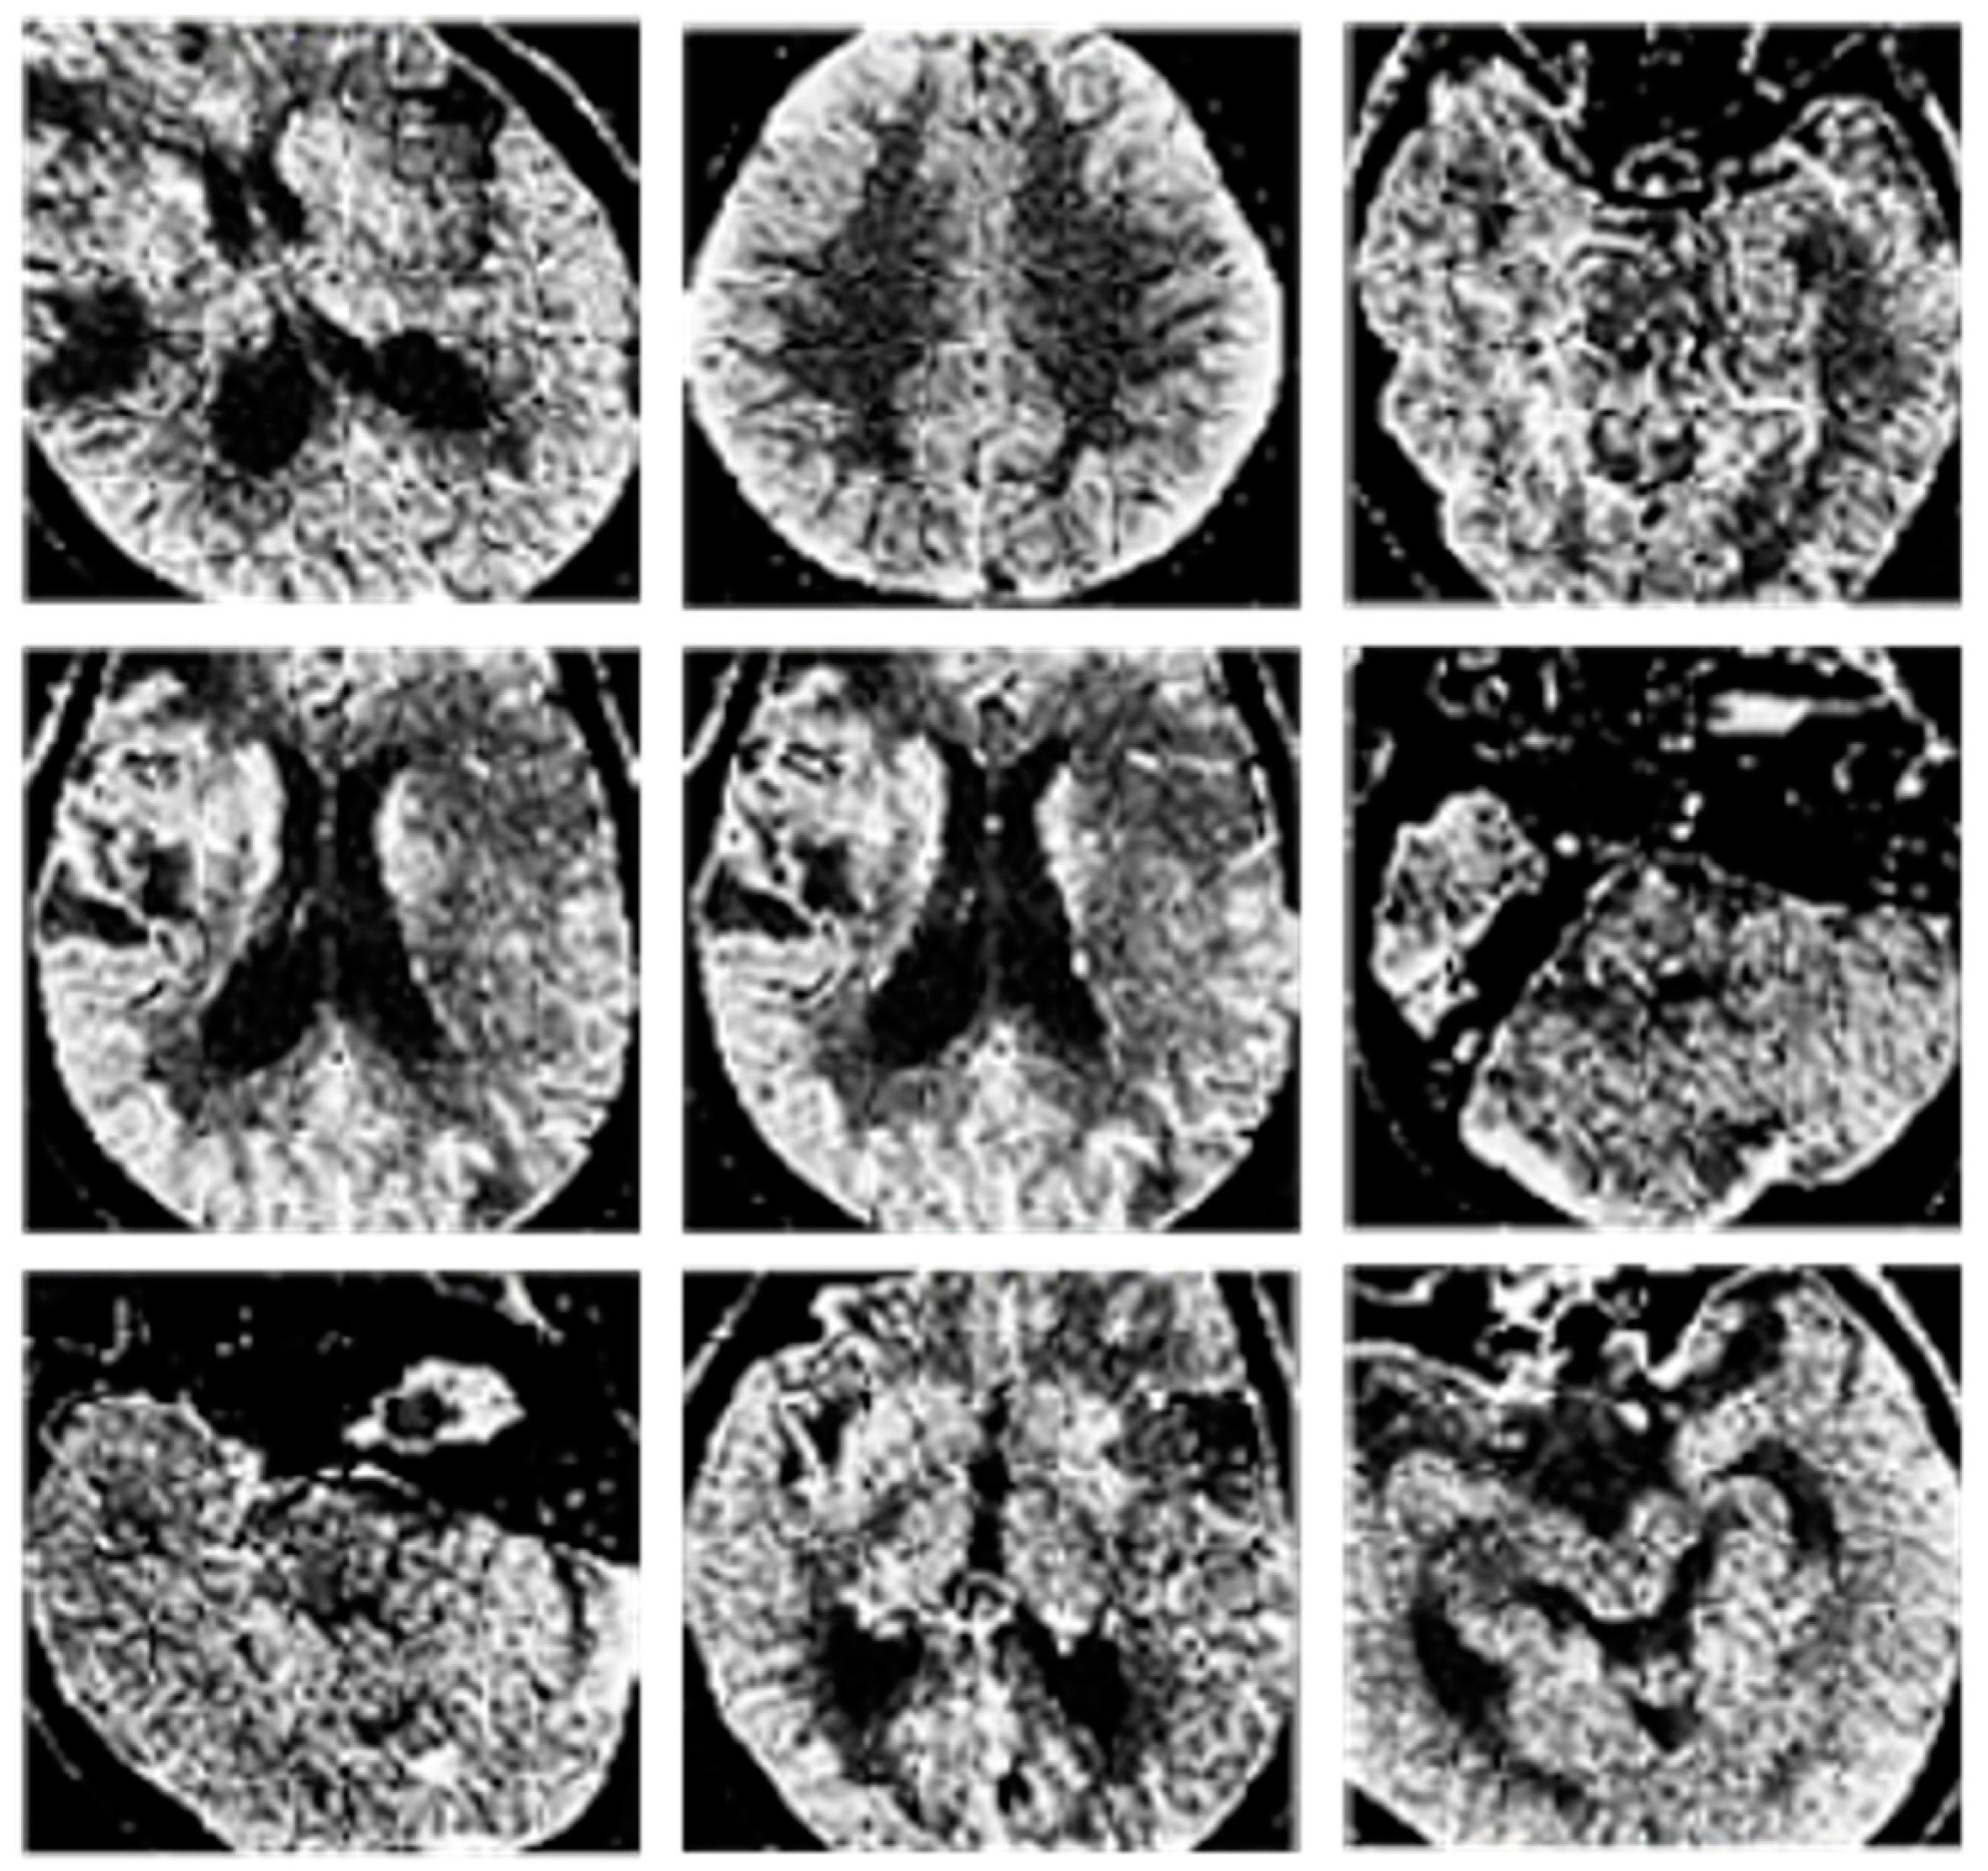

Examples of the classification results are provided in Figure 5 and Figure 6.

Figure 6. Results of CT image classification. In particular, CT images without artifacts.